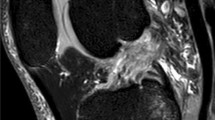

Lateral tibial slope (LTS) were measured on sagittal MRI sequences according to the method described by Hudek et al. [22] (Fig. 2). This method has been reported to be the most repeatable method to measure sagittal tibial slopes on MRI and is independent of proximal tibial length [23]. First, the proximal anatomical axis of the tibia was defined on the central sagittal slice in which the attachment of the PCL and the intercondylar eminence were visualized, and both the anterior and posterior tibial cortices appeared in a concave shape. Within this slice, two circles were placed into the proximal tibia. The proximal circle was fit within the proximal, anterior, and posterior cortical borders. The distal circle was fit within the anterior and posterior cortices with the center of the circle positioned on the perimeter of the proximal circle. A line drawn through the centers of both circles defined the proximal anatomical axis of the tibia. Next, the sagittal slice showing the center of the PLL and PLC segment of the lateral plateau were identified. In the PLL as well as in the PLC a tangent to the uppermost even part between the superior anterior and posterior cortices was drawn. For the cartilaginous slope, the tangent was applied to the cartilage layer seen on MRI. The PLL slope, as also the PLC slope, was defined as the angle between the orthogonal to the proximal anatomic axis of the tibia and the tangent. All measurements were made in digital at our PACS system.

Measurement of tibial slope in the PLC and PLL segment according to Hudek et al. in a 31-year-old healthy woman. It shows the determination of the tibial shaft axis. The white line represents the tibial shaft axis and is defined by the centers of the two red circles. The proximal red circle is bounded by the anterior and posterior corticalis and the tibial plateau. The distal red circle is bounded by the anterior and posterior corticalis and the center of the circle lies on the circumference of the proximal circle; II sagittal MRI in the center of the PLC segment, the yellow line is the tangent representing the cartilaginous slope and the blue tangent represents the bony slope; III sagittal MRI in the center of the PLL, again the yellow line represents the tangent presenting the cartilaginous slope and the blue one the bony slope